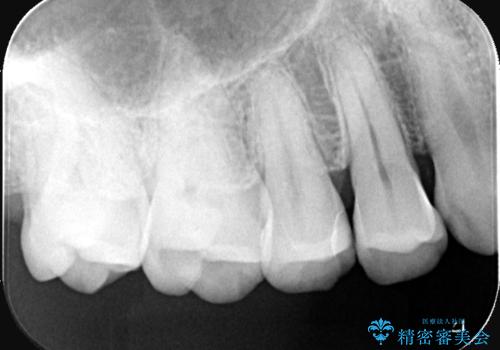

右上5番にう蝕があり、審美性・適合性・材料安定性の高いセラミックインレーでのやり替えとなりました。

右上5番の近遠心にう蝕が認められたため、CR裏層の後MOD窩洞のセラミックインレーとしました。

インレーセット時はラバーダム防湿を行っています。